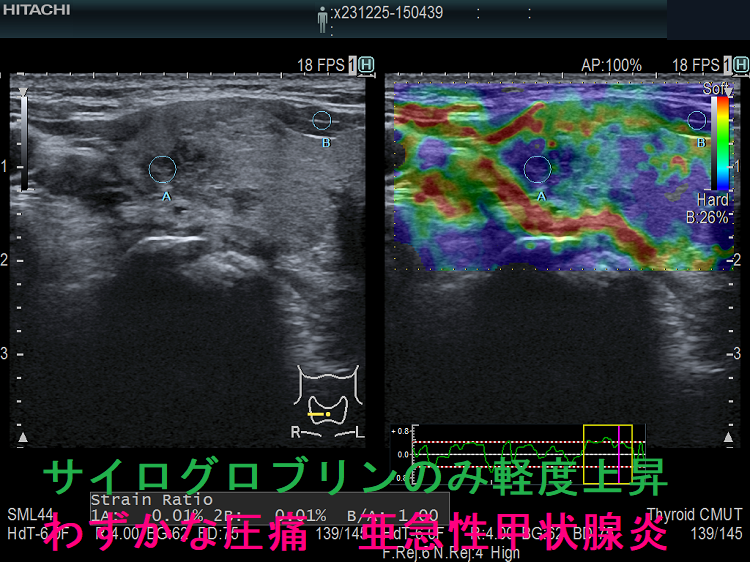

また、下の画像は、甲状腺機能正常橋本病患者において、特に自覚症状ないものの、数年来正常だったサイログロブリンのみが軽度上昇。原因を調べるため行った甲状腺超音波(エコー)検査で、亜急性甲状腺炎が見つかりました。低エコー部を圧迫すると、患者自身も気が付かなかった軽度の圧痛あり。

発熱、頸部腫脹と疼痛・圧痛、圧痛部に一致した低エコー域、炎症反応を認め、典型的な亜急性甲状腺炎だが、甲状腺機能正常で甲状腺中毒症は無く、サイログロブリンだけ上昇するケースもあります。

「痛みを伴う」初期段階の亜急性甲状腺炎において、血清サイログロブリン値は、亜急性甲状腺炎の程度や甲状腺ホルモン濃度とは無関係に、92%の患者で上昇します。[Arch Intern Med. 1985 Feb;145(2):243-7.]